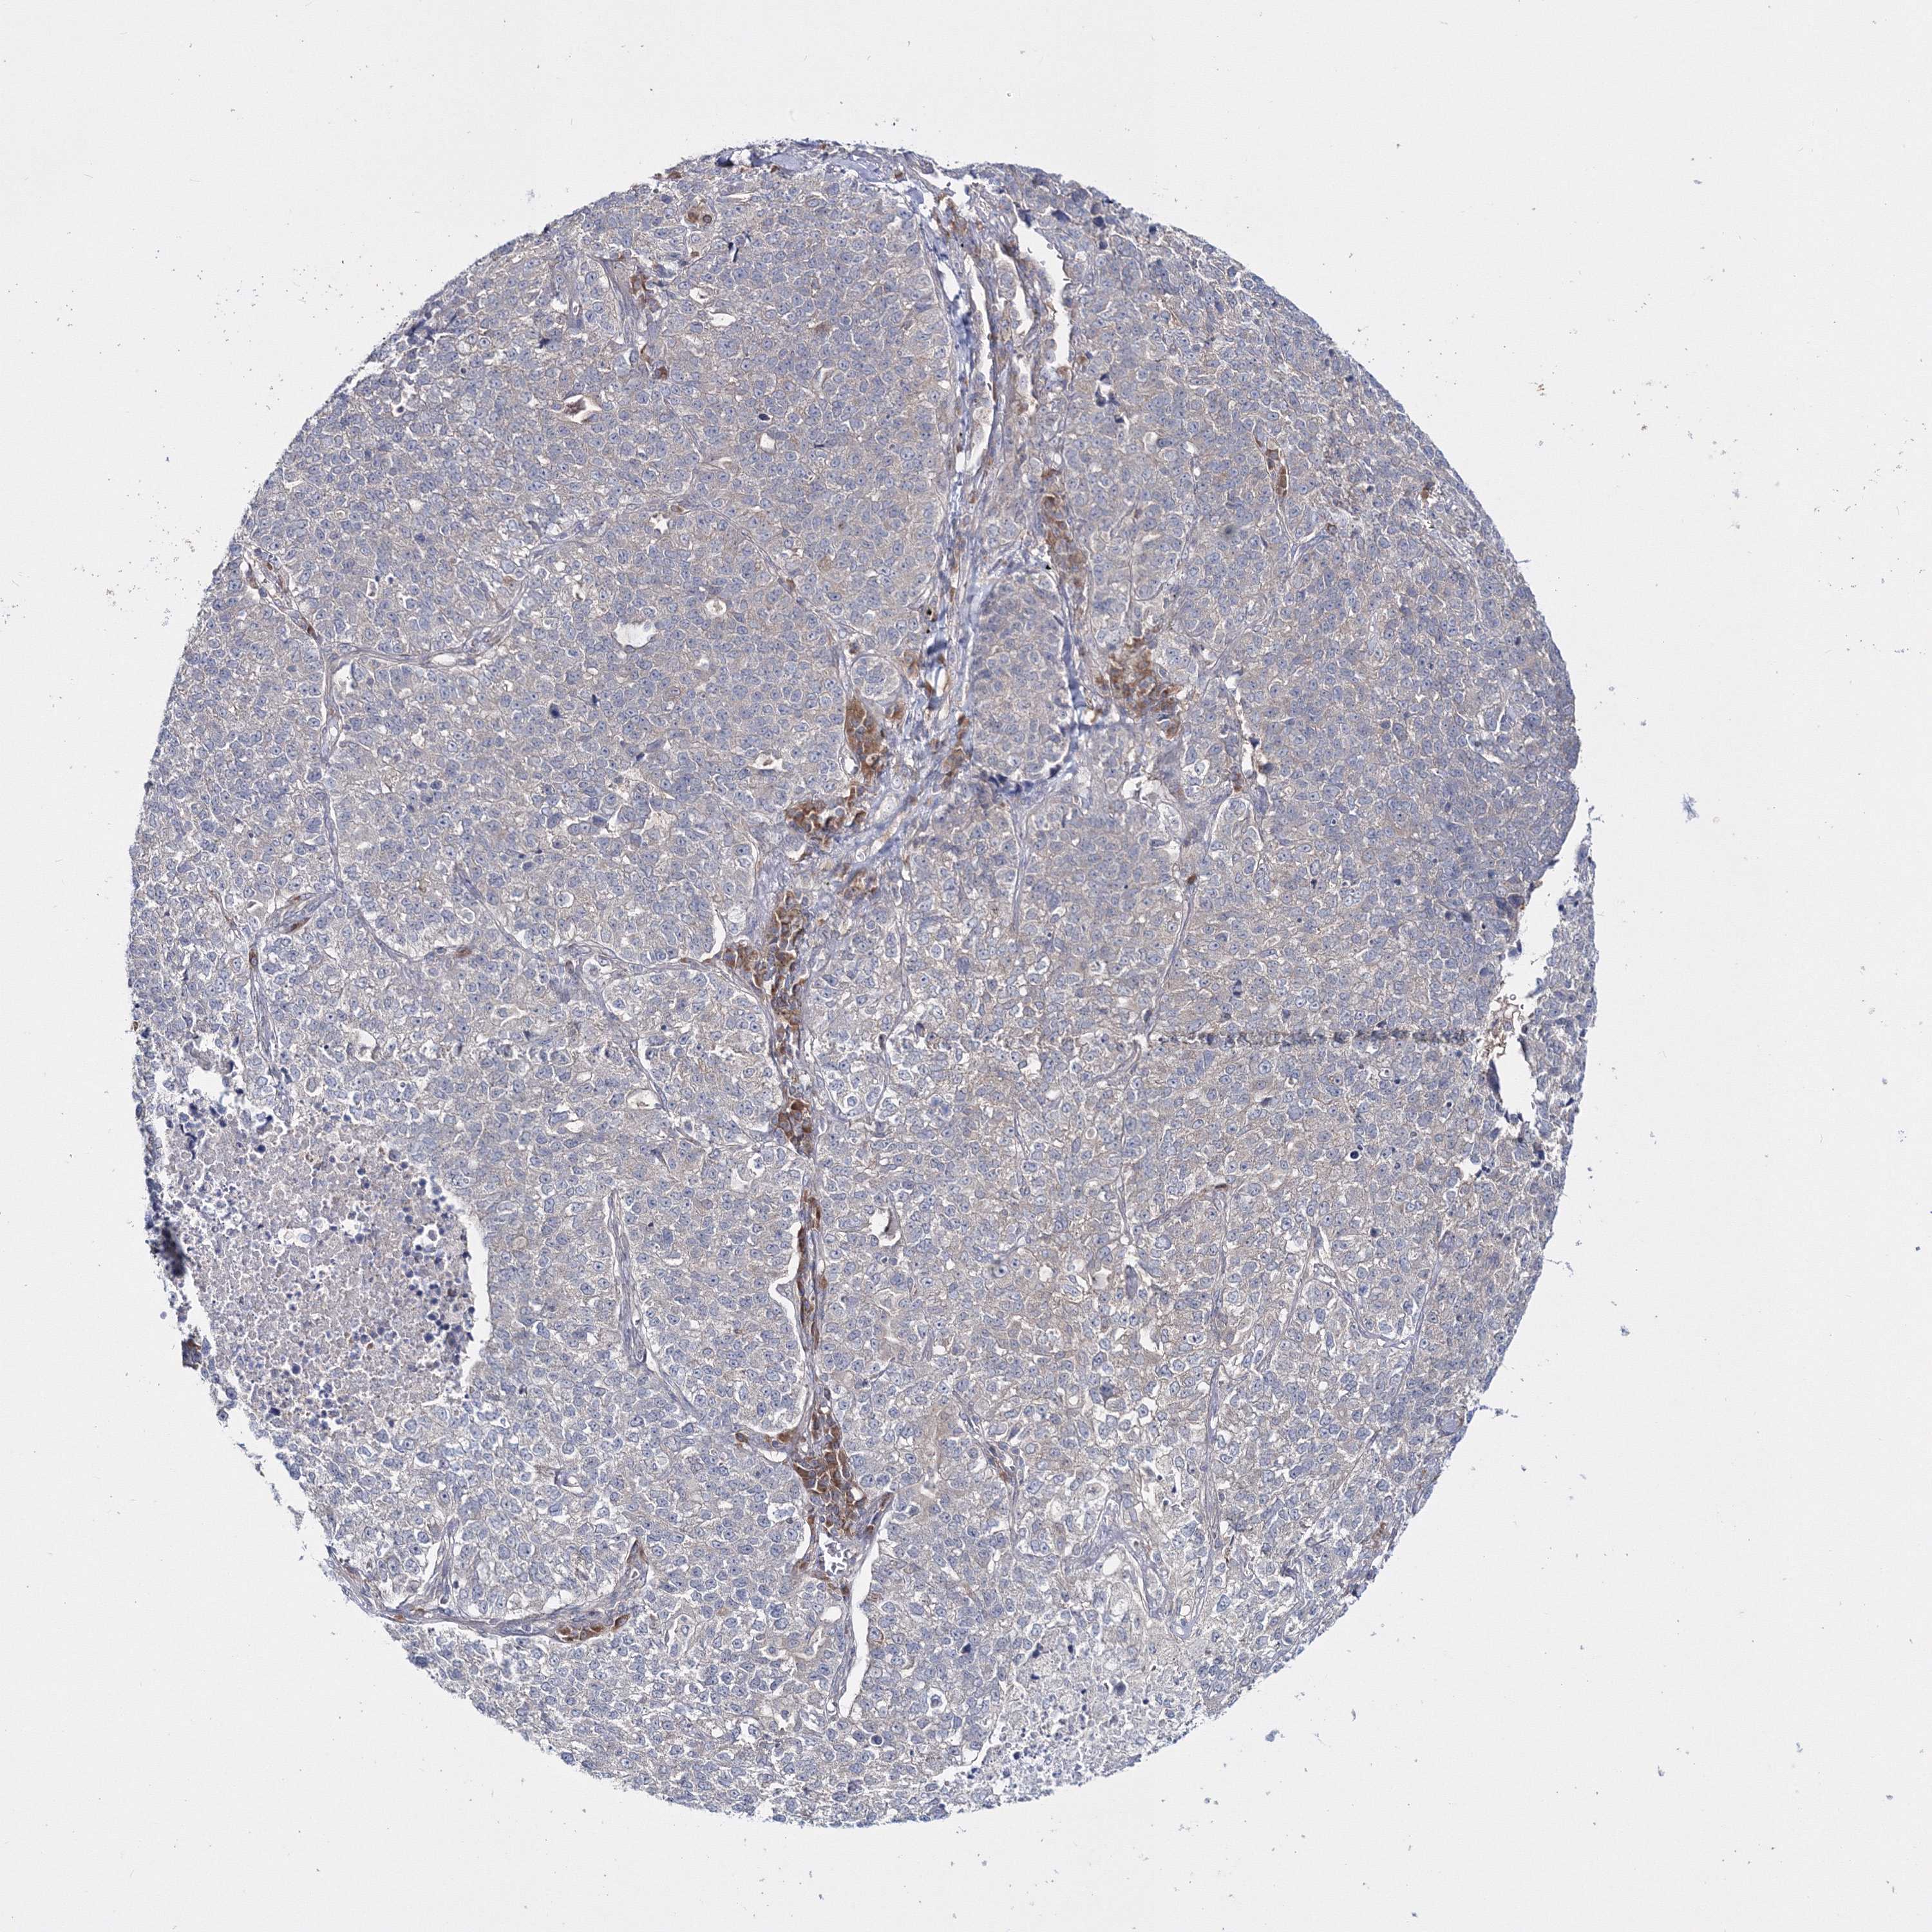

LUNG ADENOCARCINOMA (TCGA) - Interactive survival scatter ploti

The Survival Scatter plot shows the clinical status (i.e. dead or alive) for all individuals in the patient cohort, based on the same data that underlies the corresponding Kaplan-Meier plots. Patients that are alive at last time for follow-up are shown in blue and patients who have died during the study are shown in red.

The x-axis shows the expression levels (FPKM) of the investigated gene in the tumor tissue at the time of diagnosis. The y-axis shows the follow-up time after diagnosis (years). Both axes are complimented with kernel density curves demonstrating the data density over the axes. The top density plot shows the expression levels (FPKM) distribution among dead (red) and alive patients (blue). The right density plot shows the data density of the survived years of dead patients with high and low expression levels respectively, stratified using the cutoff indicated by the vertical dashed line through the Survival Scatter plot. This cutoff is automatically defined based on the FPKM cutoff that minimizes the p-score. The cutoff can be changed by dragging the vertical line or by entering a cutoff value in the square labeled "Current cut-off".

Under the Survival Scatter plot the p-score landscape (black curve; left axis) is shown together with dead median separation (red curve; right axis). Dead median separation is the difference in median mRNA expression between patients who have died with high and low expression, respectively. It is calculated as follows: median FPKM expression of dead patients with high expression - median FPKM expression of dead patients with low expression. This is intended to aid the user in visually exploring custom cutoffs and the associated p-scores and dead median separation.

Individual patient data is displayed and can be filtered by clicking on one or more of the category buttons on the top of the page. Categories describing expression level and patient information include: high, low, alive, dead, female, male and tumor stages. The scale of the x-axis can be toggled between linear and log-scale by clicking on the "x log" button. Mouse-over function shows TCGA ID, patient information and mRNA expression (FPKM) for each patient.

& Survival analysisi

Kaplan-Meier plots summarize results from analysis of correlation between mRNA expression level and patient survival. Patients were divided based on level of expression into one of the two groups "low" (under cut off) or "high" (over cut off). X-axis shows time for survival (years) and y-axis shows the probability of survival, where 1.0 corresponds to 100 percent.

IPMK is not prognostic in Lung Adenocarcinoma (TCGA)

: 4.8